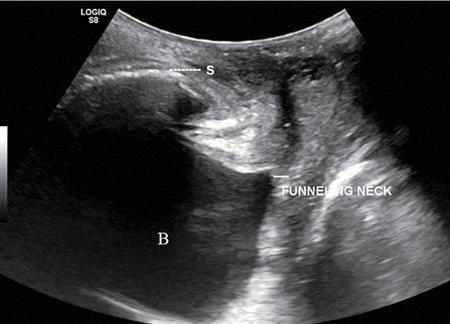

PELVIC FLOOR IMAGING – ANTERIOR AND MIDDLE COMPARTMENTS Anu Epean, Deepa Korula The term ‘Pelvic floor disorder’ refers to dysfunction of the pelvic floor musculature and connective tissues which provide support for the pelvic organs. This can produce a wide range of symptoms such a urinary incontinence, straining to void, dyspareunia, constipation, faecal incontinence and organ prolapse. The greatest risk factors for pelvic floor disorders are female sex and advanced age. Other risk factors include obesity, pregnancy, multiparity, smoking, connective tissue disorders. The pelvic floor is broadly divided into three compartments. The bladder and urethra form the anterior compartment. The vagina and uterus form the middle compartment and the posterior compartment comprises of the rectum and anal canal (Fig. 7.16.1.1). The attachment of the fascia, muscles and the ligaments to the bony pelvis form the support for these structures. From cranial to caudal, there are three layers which make up the pelvic floor – the endopelvic fascia, the pelvic diaphragm and urogenital diaphragm. This is the most cranial layer of pelvic floor, lying deep to peritoneum. It is a fine structure, comprising of a network of connective tissue which encases the pelvic viscera, provides support to the pelvic organs and maintains their anatomic relationship. There are several condensations of this fascia and ligaments which provide support in each of the pelvic compartments. In the anterior compartment, a fascial condensation called pubocervical fascia extends from anterior vaginal wall to the pubis. Tear in the pubocervical fascia can cause cystocele and urinary incontinence. There are three groups of ligaments which provide urethral support – periurethral, paraurethral and pubourethral ligaments. The periurethral ligaments arise from medial fibres of pubococcygeus and pass ventral to urethra. The paraurethral ligaments connect the lateral wall of urethra to periurethral ligament and pubourethral ligament connects the lateral wall of urethra to arcus tendineus. The urethra lies on a Hammock-like supportive layer of endopelvic fascia and anterior vaginal wall, which are stabilized by attachment laterally to arcus tendineus and levator ani (Fig. 7.16.1.2). In the middle compartment, condensations of the endopelvic fascia which attach the uterus to the lateral pelvic wall is called parametrium, which is made up of the uterosacral and cardinal ligaments. The uterosacral cardinal ligament complex supports and suspends the cervix and upper vagina above the levator plate. More inferiorly, the paracolpium attaches the vagina to the lateral pelvic wall. There are three levels of fascial support to the vagina: In the posterior compartment, the perineal body located within the rectovaginal septum supports ligaments and muscles and prevents abnormal widening of levator hiatus (Fig. 7.16.1.3). The rectovaginal fascia extends from posterior wall of vagina to anterior rectal wall. A tear in the rectovaginal fascia is the cause for an anterior rectocele. Arcus tendineus levator ani (ATLA) is formed by the condensation of the endopelvic fascia laterally, along the pelvic sidewall. This extends obliquely from inferior pubic symphysis to ischial spine and provides lateral support to the pelvic organs and attachment of the levator ani. Fascial condensations are not visualized on imaging; however, organ prolapse, due to deficiency in any of these, can be detected on MRI. The levator ani and the coccygeus muscles make up the pelvic diaphragm. The levator ani is the primary muscle of the pelvic diaphragm and is attached to the pubis and to the ATLA laterally on both sides. The slow twitch fibres of the levator ani continuously contract, maintaining tone to the pelvic floor and suspending the pelvic organs in the correct position. The two most important components of the levator ani are the iliococcygeus and puborectalis muscles. The iliococcygeus arises from external anal sphincter and has a curved shape, concave inferiorly. It fans out laterally to its insertion in the posterior part of arcus tendineus (Fig. 7.16.1.4A and B). Posteriorly, in the midline, condensations of ilococcygeus form a firm raphe anterior to coccyx called the anococcygeal ligament or levator plate. The pubococcygeus muscle is a component of the levator ani. It forms the anteromedial part and is a thick bundle of fibres arising from the pubis and anterior portion of arcus tendineus. It extends horizontally back to behind the rectum, medially forming the margin of urogenital hiatus (Fig. 7.16.1.5A). The anorectal and urogenital hiatus are closed by the contraction of the pubococcygeus muscle. This enables support during rest and in situations where the intraabdominal pressure is increased. The medial fibres of pubococcygeus, depending on their attachment to urethra, vagina, anus and rectum are termed as pubourethralis, pubovaginalis, puboanalis and puborectalis, collectively as pubovisceralis. The puborectalis forms a sling around the rectum (Fig. 7.16.1.5B). The muscles of the pelvic diaphragm are well delineated on MRI. The urogenital diaphragm or perineal membrane is the most caudal layer of the pelvic floor. It has a triangular appearance, extending from the pubic symphysis and the ischiopubic ramus to the posterior perineal body. It is ventral to the external anal sphincter and perineal body. It is attached to the surrounding structures such as the perineal body, external anal sphincter, vagina and the bulbocavernosus muscle. Imaging has an increasing role in the evaluation of pelvic floor disorders. Clinical examination alone has a low sensitivity and specificity for the detection of multicompartment involvement and organ prolapse. Imaging helps to detect involvement of multiple pelvic compartments and thus to plan surgery. Ultrasound, MRI and conventional imaging which includes voiding cystourethrography, evacuation proctography and dynamic cystocolpoproctography (DCP) are used to evaluate the pelvic floor. It is easily available, cheap and does not involve ionizing radiation. In the evaluation of the anterior compartment, ultrasound is more reliable than MRI. Transperineal ultrasound using 2D, 3D or 4D techniques along with dynamic imaging helps to evaluate pelvic floor dysfunction. Patient is placed in a dorsal lithotomy position for a transperineal scan although a standing position can also be used. Convex transducer (2–6 MHz) or endoluminal transducers (endovaginal/endorectal) maybe used. In a midsagittal translabial scan, the anatomic relationship of urethra, bladder, vagina, cervix and anorectum can be studied and the relative position of these organs determined by use of certain measurements. The bladder-symphysis distance (BND) is the distance between the bladder neck and lowest margin of symphysis pubis and demarcates position of the bladder neck. Measurement of BND is made at rest and during Valsalva manoeuvre and the difference in BND between the two, gives the measure of bladder neck descent. There are no definite values to indicate normal descent but there is a proposed cut off of 20, 25, 30 mm to indicate hypermobility (Fig. 7.16.1.6A and B). The proximal urethra rotates posteroinferiorly during Valsalva manoeuvre and this can be measured by the posterior urethrovesical angle (β) or the gamma angle. The posterior urethrovesical or retrovesical angle (β) is the angle between a line through the urethral axis and the line through the trigonal surface of the bladder and varies from 90–120 degrees normally. This may increase to 160–180 degrees and can be associated with funnelling of bladder neck. The gamma angle is the angle between a line through the inferior margin of pubic symphysis and the urethrovesical junction. This is seen on Valsalva manoeuvre or at rest in patients with stress incontinence (Fig. 7.16.1.7). Color Doppler can demonstrate urine leakage on performance of Valsalva or at rest. Other abnormalities that can be detected on transperineal ultrasound are cystocele, urethral diverticulum, Gartner duct cyst, foreign body or bladder tumour. 3D pelvic ultrasound is useful to evaluate pelvic floor dysfunction and to study the urethra, levator ani complex, paravaginal supports, prolapse and implant imaging. 4D ultrasound helps in real-time, dynamic imaging of pelvic floor. In the middle compartment, although uterine prolapse is often clinically evident, it can also be detected by ultrasound. Uterine prolapse can be also quantified by measuring maximum descent of uterus from the reference point which is the inferior margin of pubic symphysis. Ultrasound is also useful to evaluate for surgical planning in a large retroverted uterus with an anteriorly placed cervix causing voiding symptoms. MRI is useful in the evaluation of pelvic floor as it provides good anatomic detail about the pelvic floor muscles, ligaments because of its inherent superior soft tissue resolution. In addition, dynamic MRI yields functional information. MRI defecography is a dynamic study performed to study the posterior pelvic compartment but it also gives information about the anterior and middle compartments. It can be performed both with closed magnet and open magnet systems. The patient is positioned supine with phased array coil around pelvis in a closed magnet system. In an open magnet system, the patient is in a sitting and more physiological position; however, due to the lower signal to noise ratio and lower resolution, a closed magnet system is preferred. Bowel preparation with use of laxative on night before the scan is optional. Voiding prior to the study is encouraged since an overdistended bladder can cause misinterpretation of results. Presence of some urine in the bladder is however, helpful to detect anterior vaginal prolapse. Instructions are given to the patient, prior to the procedure, about the ‘rest’, ‘squeeze’, ‘strain’ and ‘defecate’ phases of dynamic imaging, to ensure that movement or lifting of the pelvis does not occur during these manoeuvres. The rectum is filled with up to 200 mL of ultrasound gel. The patient is made to wear an adult diaper and covered with an incontinence pad on the gantry. Vaginal gel, ∼50 mL maybe introduced since this helps to delineate anatomic landmarks and detect uterovaginal prolapse. Initial large FOV T1 localizer scans help to identify the midline sagittal section of pelvis. T2-weighted fast spin echo, high-resolution sequences in sagittal, axial, coronal planes are used to obtain anatomic detail. This is followed by dynamic imaging of the pelvic floor with use of steady state imaging sequences such as True fast imaging with steady state precession (TrueFISP Siemens) and balanced fast field echo (balanced FFE Philips). Steady state sequences have the advantage of short acquisition times and higher signal to noise ratio and hence useful to obtain rapid serial midsagittal images while patient performs ‘squeeze’, ‘strain’ and ‘defecates’. There are several points and lines for measuring and staging pelvic organ prolapse on MRI; however, the PCL line is said to have the highest interobserver and intraobserver reliability of MRI measurements compared to all proposed reference lines and is described below: Pubococcygeal line (PCL): defined as the line that connects the inferior portion of the pubic symphysis to the last coccygeal joint. The PCL is the most commonly used reference line for the assessment of pelvic floor disorders (Fig. 7.16.1.8).